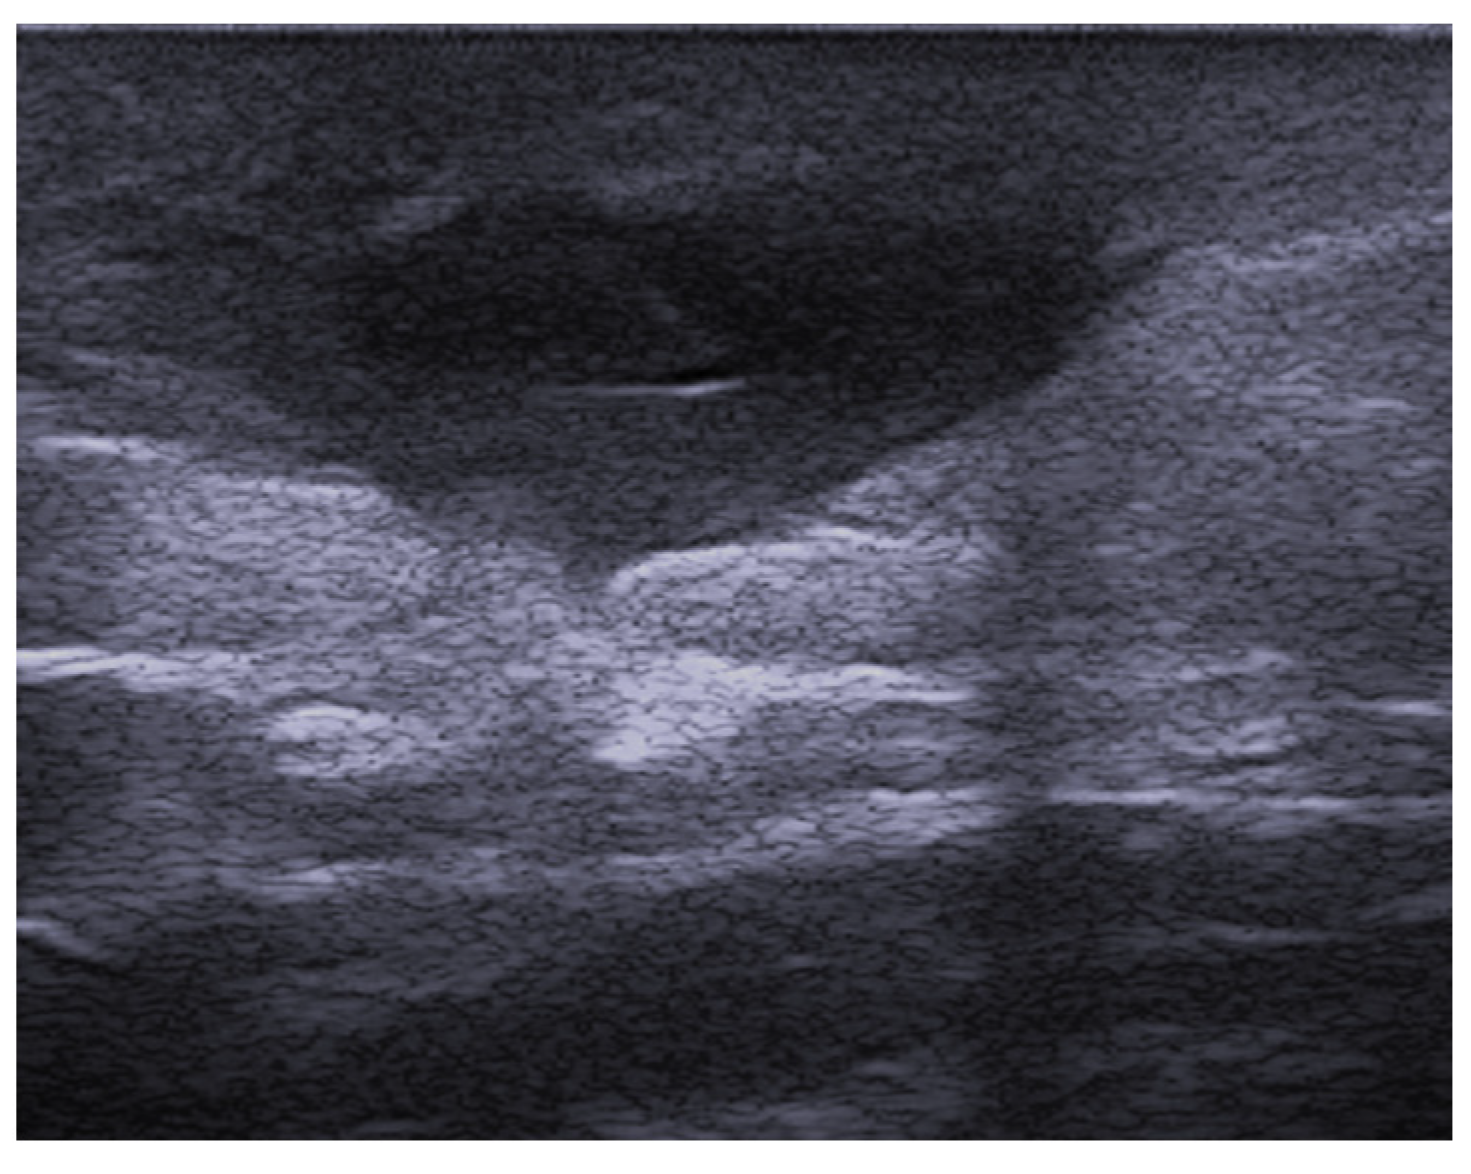

2. Infections